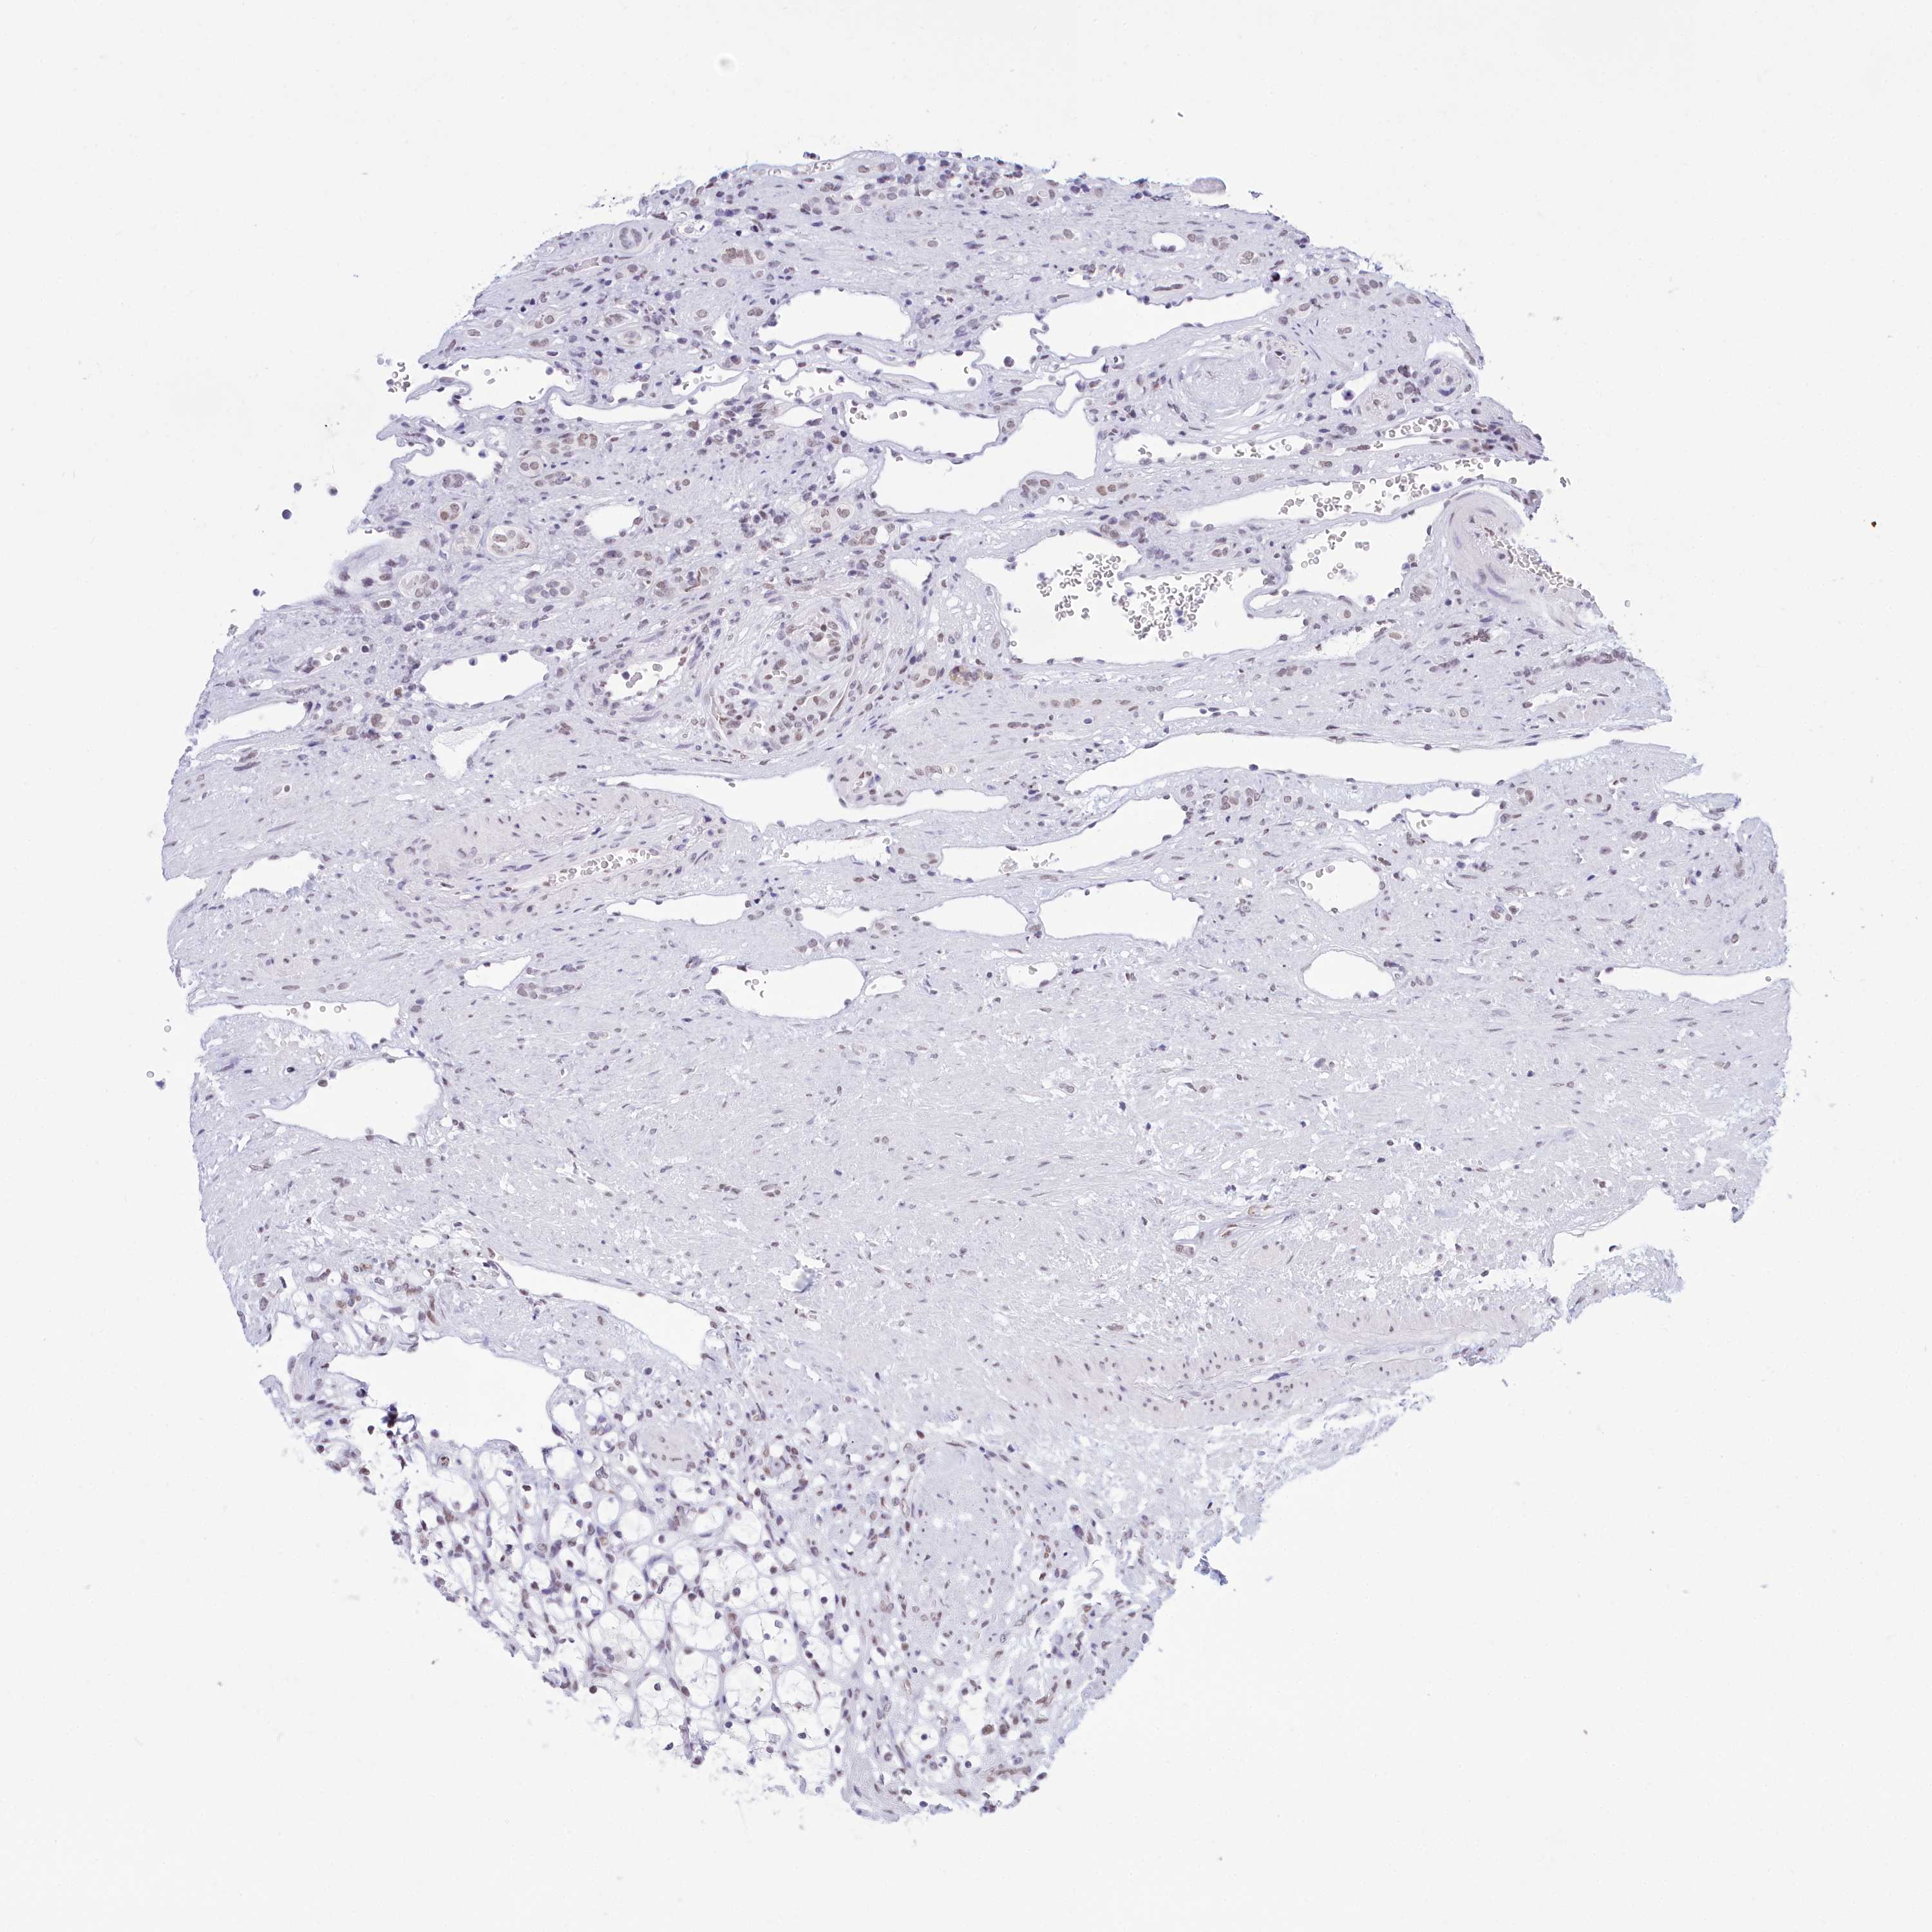

CANCER RENAL CANCER Show tissue menu

KICH TCGA KIRC TCGA KIRC VALIDATION KIRP TCGA PROTEIN RCC CPTAC PROTEIN EXPRESSION